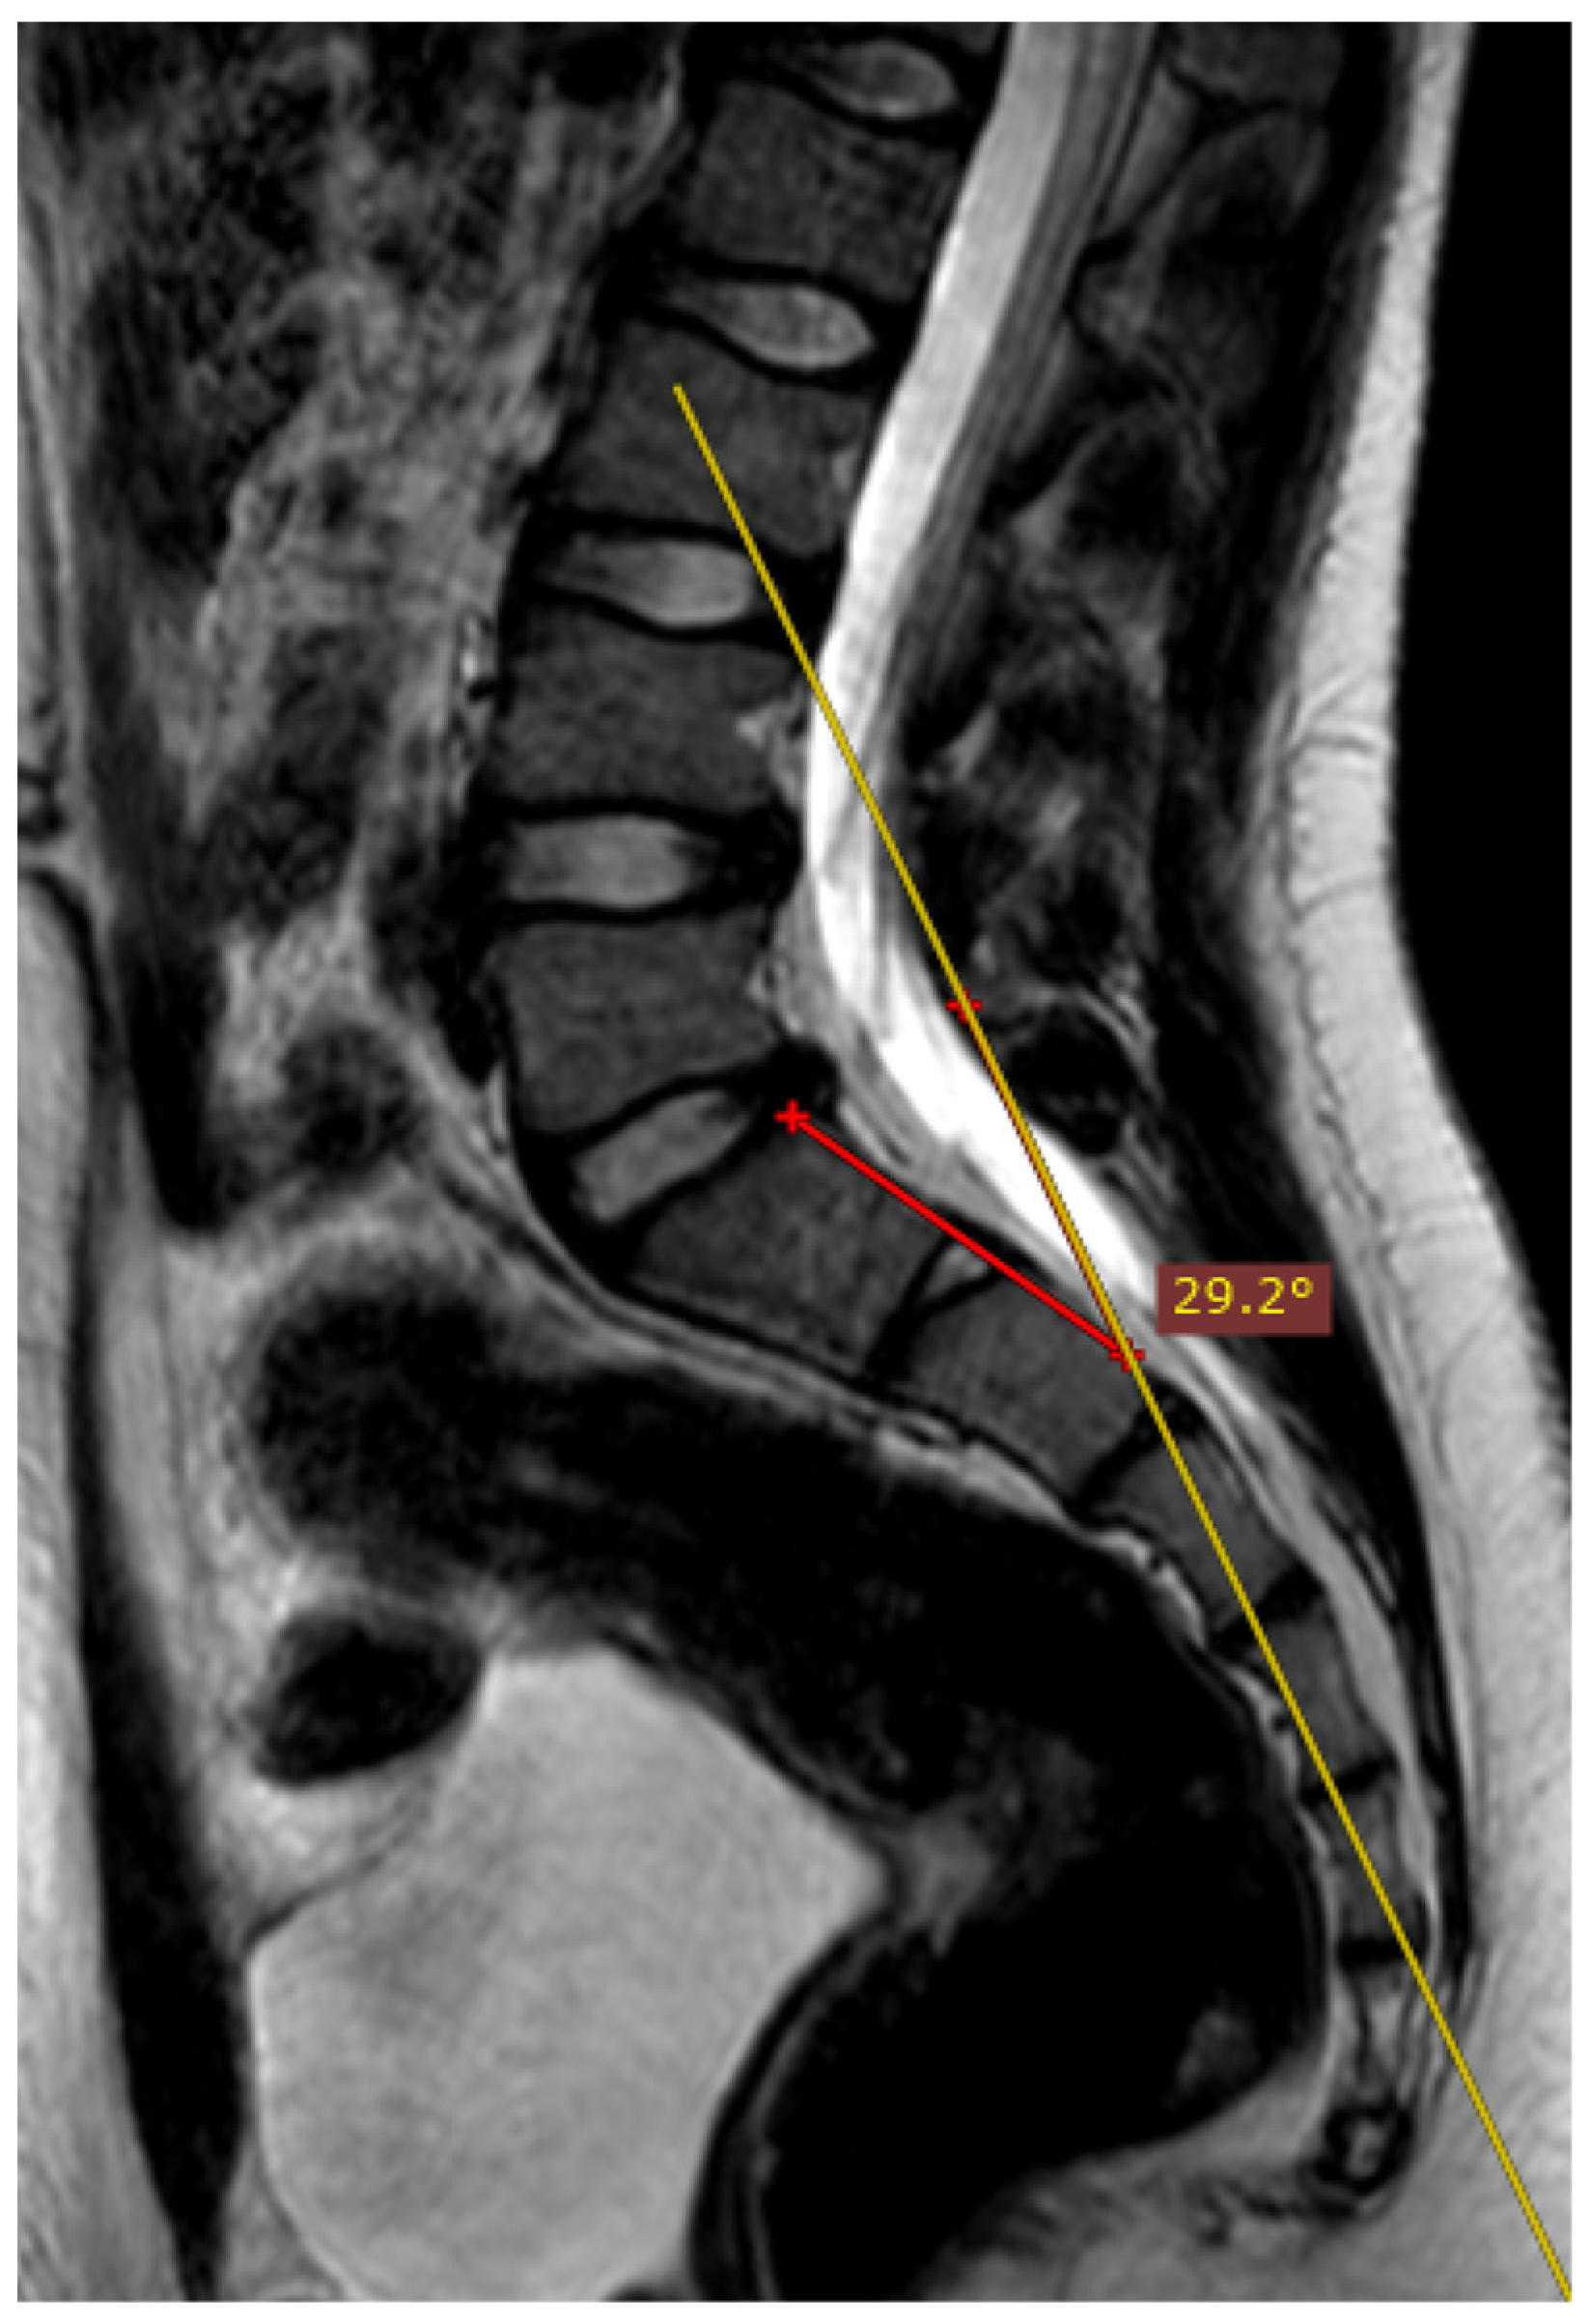

Overall, 20% (n = 35) of the examinations included in the study were performed perfectly correctly considering the technical aspect of the MRI procedure. The examination was defined as fully correct if the deviation angle measured by all of the researchers equaled 0 degrees (Figure 4). The median deviation angle was equal to 5.7 degrees. The maximal deviation angle measured was 29.2 degrees (Figure 5). The ICC (2, 2) was computed as 0.9960 (95% CI [0.9945, 0.9970]), which indicates excellent reliability between the researchers when measuring the deviation angle. Additionally, Figure 6 represents a Bland-Altman diagram with the limits of 95% agreement stated. The results of the division into quartiles due to the deviation angle measurements of all the examinations are shown in Table 1. The obtained division was considered to be valid for the whole study, and on its basis the analysis of the subsequent parts of the study was performed.

Figure 5.

The measured deviation angle equals 29.2 degrees (group 4), T2-weighted sequence. The red line is the fully correct line drawn between the posterior edges of the S1 and S2 vertebrae. The yellow line marks the actual plane in which the slices were acquired.